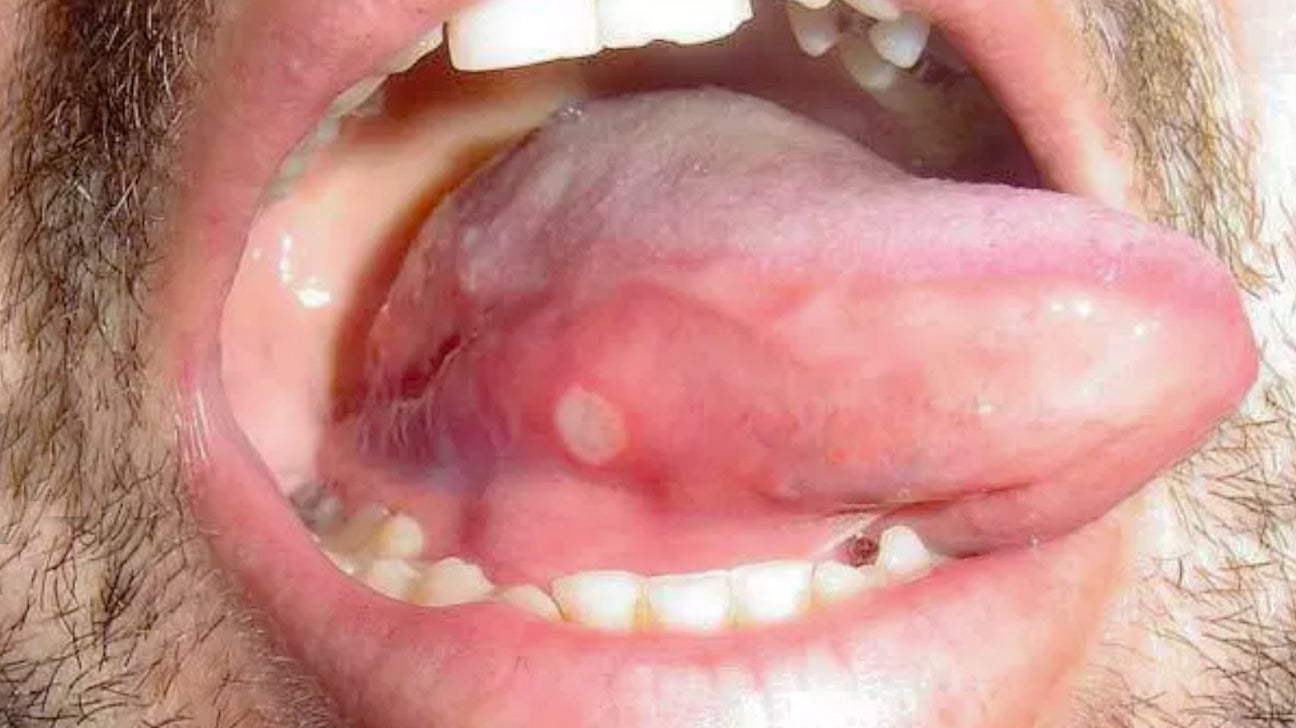

canker sore on tongue

Canker sores can also appear on the tongue.

Photo by DermNet New Zealand